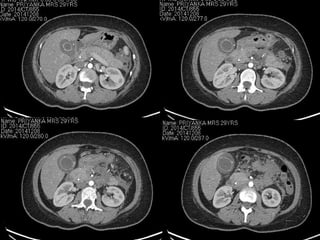

Case 1..

Contrast enhanced CT scan: (15/11/14)

• CBD with stent in situ

• Extensive fluid collection in lesser sac,

pelvis and left paracolic pouch;

- No air pockets

• Extra pancreatic fat necrosis

• Bilateral pleural effusion